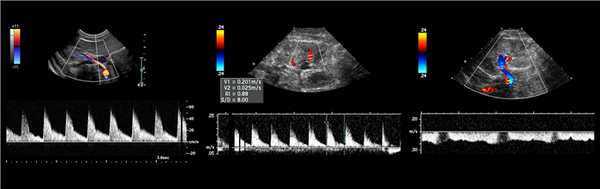

Рисунок. Спектр сосудов почки у новорожденных: почечная артерия — выраженный систолический пик и антеградным диастолический поток (1); высокое сопротивление на внутрипочечных артериях считается нормальным для новорожденных — RI 0,88 (2); почечная вена — поток антеградный с постоянной скоростью на протяжении всего сердечного цикла, минимальные дыхательные колебания (3).

Рисунок. Пациент с острой почечной недостаточностью и рефрактерной артериальной гипертензией. УЗИ брюшной аорты и почечной артерий затруднено из-за газа в кишечнике. На сегментарных артериях слева RI о,68 (1), справа RI 0,52 (2), разница 0,16. Спектр правой сегментарной артерии имеет форму tardus-parvus — время ускорения увеличено, PSV низкий, вершина округлая. Заключение: Косвенные признаки стеноза правой почечной артерии. КТ-ангиография подтвердила диагноз: в устье правой почечной артерии атеросклеротические бляшки с кальцификацией, стеноз умеренной степени.